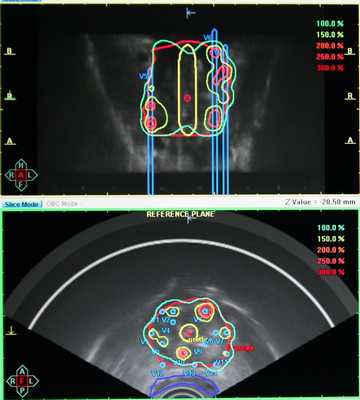

- Визуальный контроль при брахитерапии

Рис. 5. Высокомощностная (высокодозная) брахитерапия